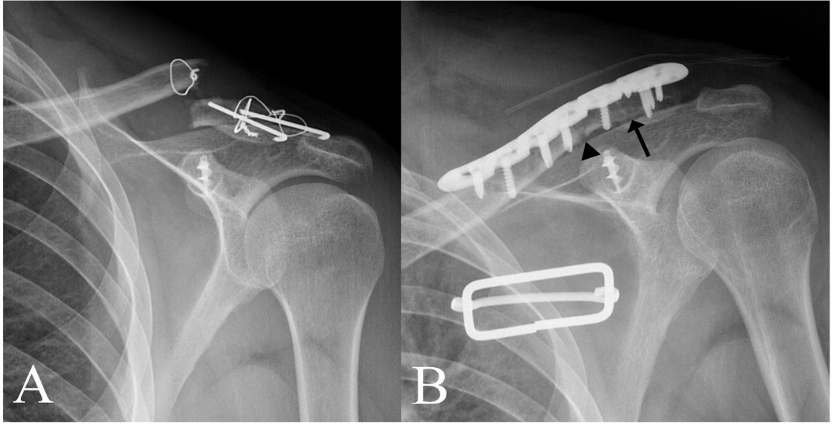

铆钉结合张力带克氏针固定

铆钉结合张力带克氏针固定后再次骨折,但转化为中段骨折,予以钢板固定

钩钢板用于锁骨远端骨折固定